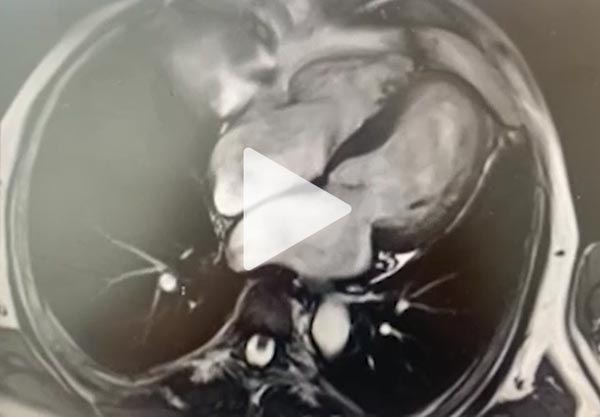

Une nouvelle réévaluation écho cardiographique

- VG dilaté (DTD 62 mm VTD 89 ml/m²) hypertrophie SIV 15 mm

- FEVG altérée 20% ,SLG altérée -15% avec un gradient base-apex >1 et septum basal-apical > 2,1

- IM modérée

- Décollement péricardique minime en regard du VG

Vidéo 10